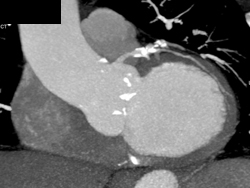

Left Internal Mammary Artery (LIMA) Graft Extends Behind Sternum